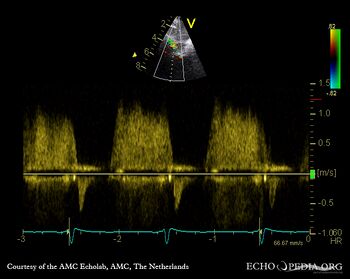

| A4CH: coronary fistula | Pulsed-wave signal of flow through coronary fistula |